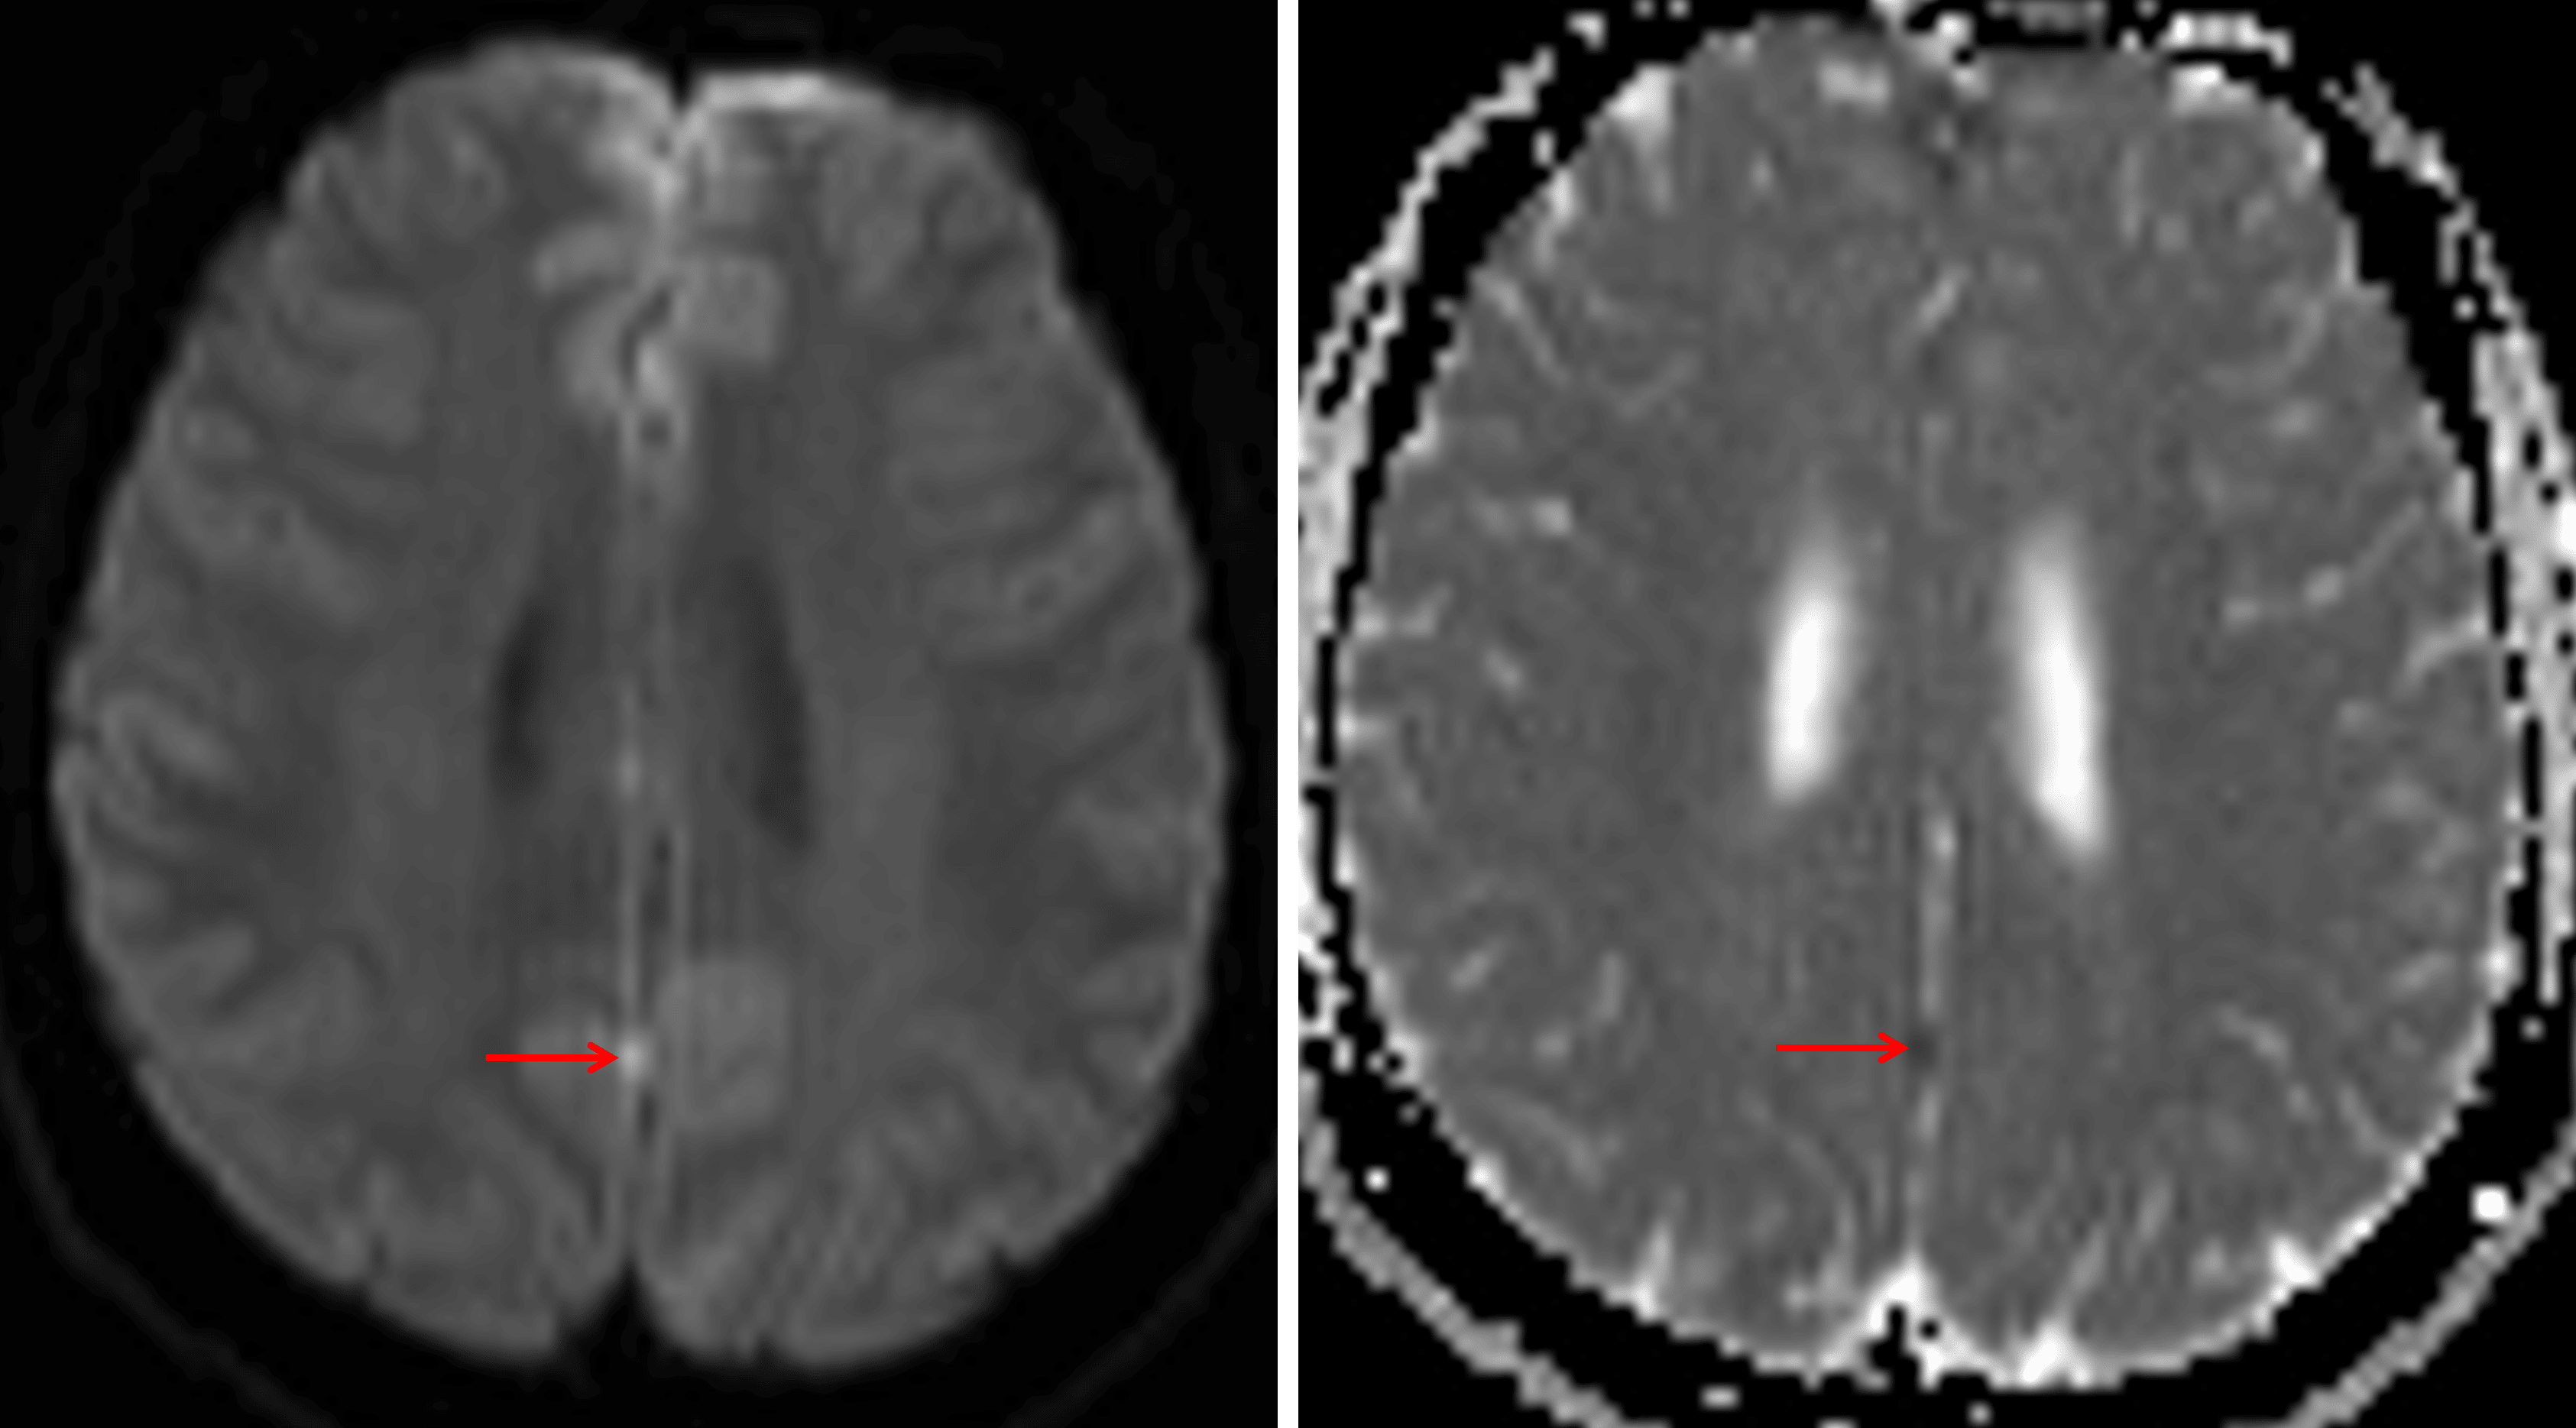

Nodular focus of restricted diffusion along the interhemispheric fissure (red arrows), which is concerning for a leptomeningeal tumor deposit.